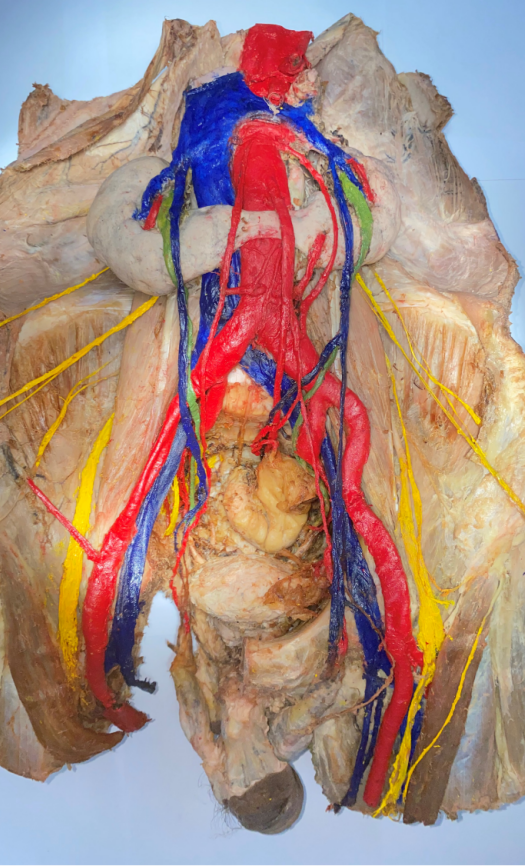

许文韬、张欣瑜、林晓婕、张宇轩、赵溱馨

《两肾相连囊肿生,腹有斑斓隙自华》